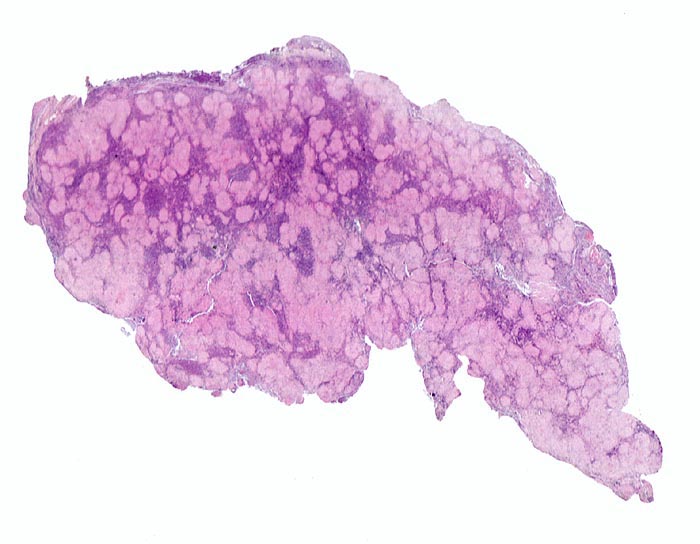

Lymphknotensarkoidose (Morbus Boeck)

Lymphknoten, inguinal

Zahlreiche helle konfluierende Granulome durchsetzen das Lymphknotenparenchym.

Vergrösserte inguinale Lymphknoten bei bekannter Sarkoidose mit Befall der Lungen.